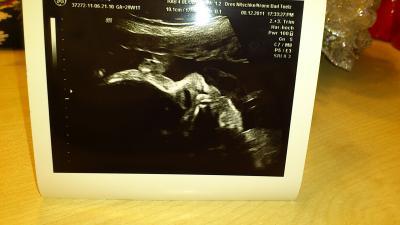

Guten abend mädels. Ich hatte ja heute wieder vu! CTG wird in 2 wochen das erstemal gemacht! Aber er hat heut wieder us gemacht. Für ein 3D bild hatte der kleine leider seine händchen vorm gesicht aber wir haben trotzdem ein schönes normales us-bild bekommen. Der kleine prinz sitzt in BEL und ist jetzt 1340g leicht und nach meiner messung 38cm "groß". Und da auch ich schon seit wochen mit vorzeitigen wehen kämpfe bin ich ab montag bis zum beginn vom MuSch am 11.1.12 krank geschrieben. Soll morgen nochmal in die arbeit und mit meiner chefin darüber reden. Damit ich nicht einfach so nicht mehr da bin. Wie findet ihr das?? Ich hab jetzt doch ein bissl ein schlechtes gewissen. Auch wenn ich weiß das es für den kleinen besser ist. Ich häng euch das bildchen noch an! Schön abend noch! Lg Mandy

Bild zu Zurück vom FA! - Forum für Februar - Mamis